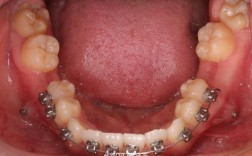

口腔正畸摄影常用类型及临床意义

| 摄影类型 | 临床意义 | |

|---|---|---|

| 口内前牙唇面照 | 上/下颌前牙唇面,包括切缘、牙龈、中线及牙齿形态 | 观察牙齿龋坏、缺损、牙龈状况,评估前牙美学及中线对齐情况 |

| 口内全牙列照 | 上/下颌全牙列,显示牙齿排列、咬合关系及牙弓形态 | 评估牙列拥挤/间隙、咬合异常(深覆合、锁合)及牙弓对称性 |

| 口内后牙咬合照 | 上下后牙颊侧咬合面,显示尖窝关系 | 判断后牙咬合功能及尖牙保护是否存在 |